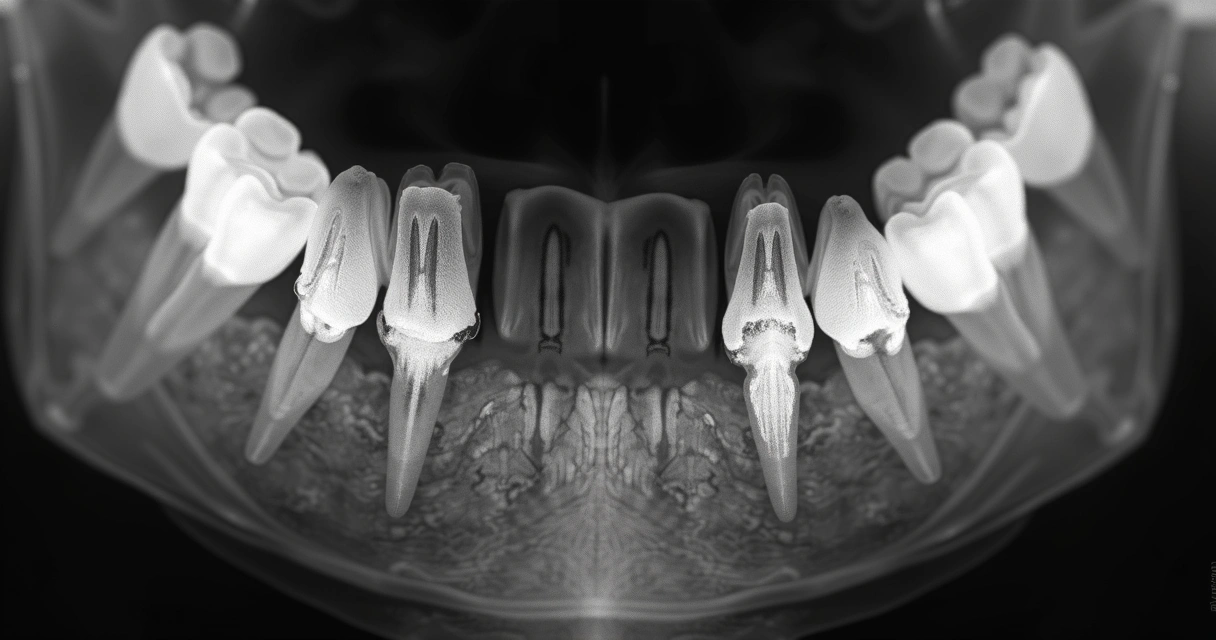

O diagnóstico é feito pelo dentista por meio de exame clínico, análise do histórico do paciente e, muitas vezes, radiografias para checar o grau de perda óssea.